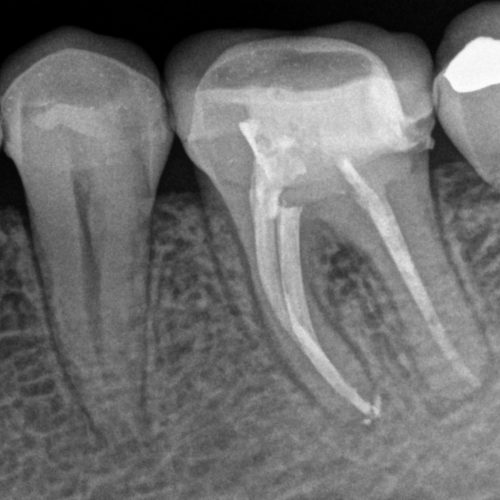

Este tratamiento consiste en eliminar la pulpa dañada, limpiar y desinfectar cuidadosamente el conducto radicular y luego sellarlo para prevenir futuras infecciones. De esta manera, el diente se mantiene en su lugar, conservando su función masticatoria, estética y evitando problemas mayores en la boca.

Si una pieza dental requiere una endodoncia, la tratamos con la máxima precisión y cuidado, utilizando las últimas tecnologías y materiales biocompatibles. Una vez que el diente está sano y libre de infección, puede convertirse en la base para otros tratamientos de rehabilitación, como: